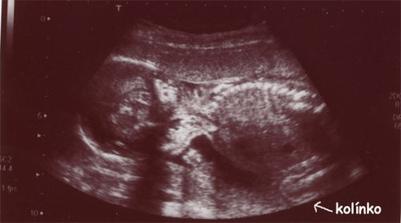

Čekání na Kateřinku... (UZ)

Čekáme holčičku - Kačenku. Dokud jsme jméno vybírali, říkali jsme jí Melounka. I.TP máme 29. 2., II.TP 2. 3. 2008. a III.TP je 13. 3. 2008.